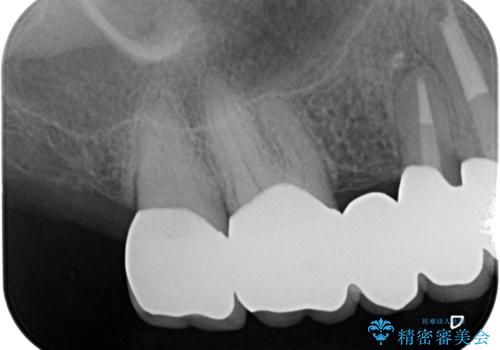

歯周ポケットの除去を併用したセラミック治療

- 110万円(ジルコニアクラウン×6・仮歯×6 歯周外科×2)費用は治療当時の料金となります

治療前に4-5mm程度あった歯周ポケットは全て2mm以内となり、非常に清掃性が高く、歯周病の再発しずらい環境に整えた上でのセラミック治療を実践することができました。